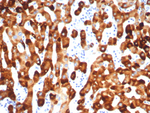

Hepatitis B Virus Surface Monoclonal Antibody (S 26)

种属

Virus

类型

Mouse Monoclonal

应用

WB IHC ICC/IF ELISA IP IM

货号 MA1-7603